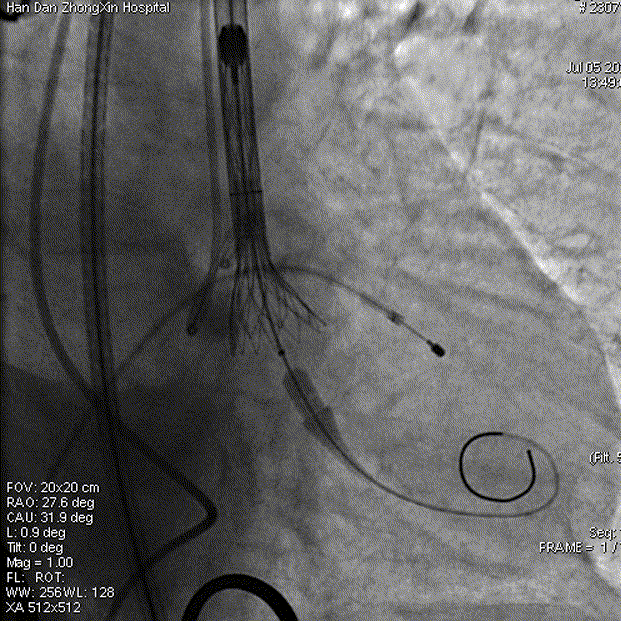

术中操作

球囊预扩

瓣膜释放

释放完成

邯郸市中心医院刘健、杨伟光、陈德峰教授术中操作

工作钢丝送入左室进行起搏,180bpm起搏下预扩张主动脉瓣,完全扩张后,主动脉根部造影无返流,回撤球囊停止临时起搏,延大鞘进入输送系统,定位输送系统位置,瓣膜释放1/3时,起搏160bpm,快速释放至3/4处,瓣膜正常工作后,观察冠脉风险。